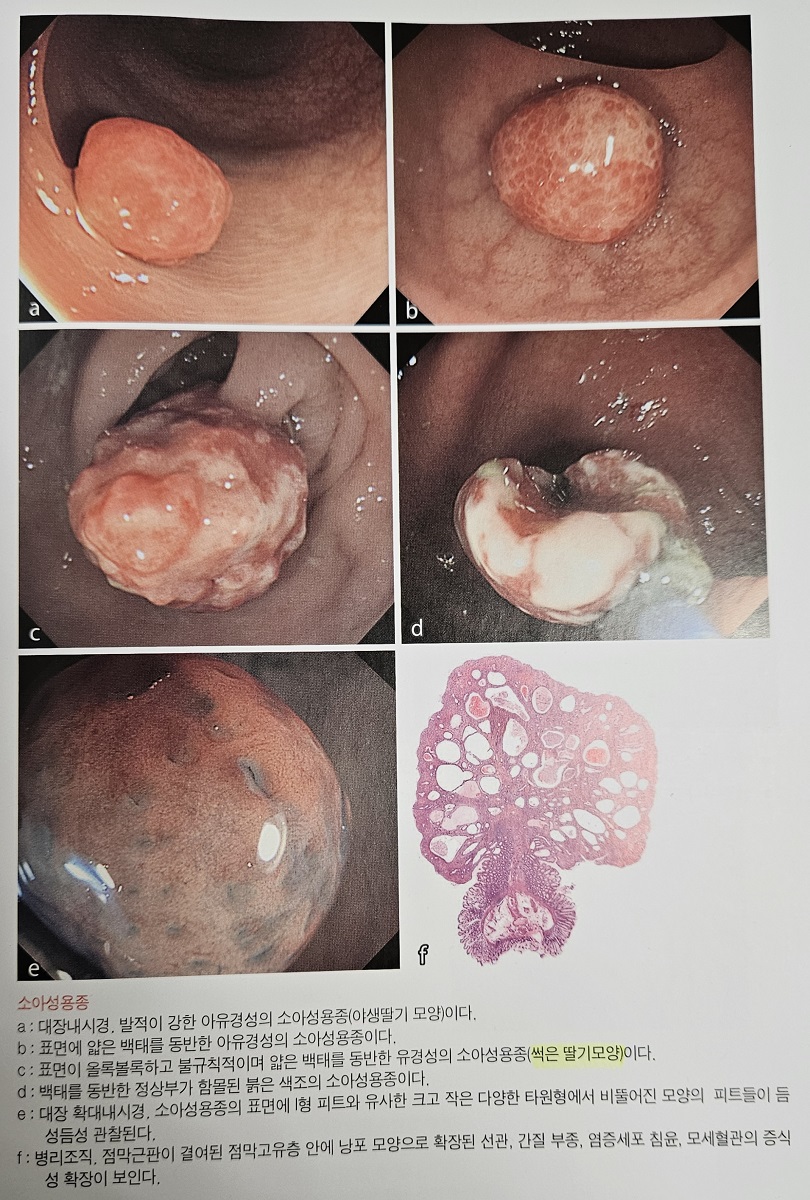

ÇÑ ÀϺ» Ã¥ ¹ø¿ªº»¿¡¼­ °¡Áö°í ¿Â ³»¿ëÀÔ´Ï´Ù. ½âÀº µþ±â ¸ð¾çÀ̶ó´Â ƯÀÌÇÑ ±â¼úÀÌ ÀÖ¾ú½À´Ï´Ù.

¿¬¼Ò¼º ¿ëÁ¾Àº ³»½Ã°æÀûÀ¸·Î ¹ÝÁú¹ÝÁúÇÏ°í ºÎµå·¯¿î Ç¥¸éÀ» °¡Áö°í ÀÖ°í Á¶Á÷ÇÐÀûÀ¸·Î ±âÁú ¼¼Æ÷¿¡ µÑ·¯ ½ÎÀÎ ³¶¼º Á¶Á÷ÀÌ Á¡¾×À¸·Î °¡µæ Â÷ ÀÖ´Â ¸ð¾çÀ» º¸À̴µ¥ ÆòȰ±ÙÀÇ Áõ½Ä¿¡¼­ ¹ß»ýÇÏ´Â °ÍÀÌ ¾Æ´Ï±â ¶§¹®¿¡ ÁøÁ¤ÇÑ ÀǹÌÀÇ °ú¿ÀÁ¾ÀÎÁö´Â ¸íÈ®ÇÏÁö ¾Ê½À´Ï´Ù.